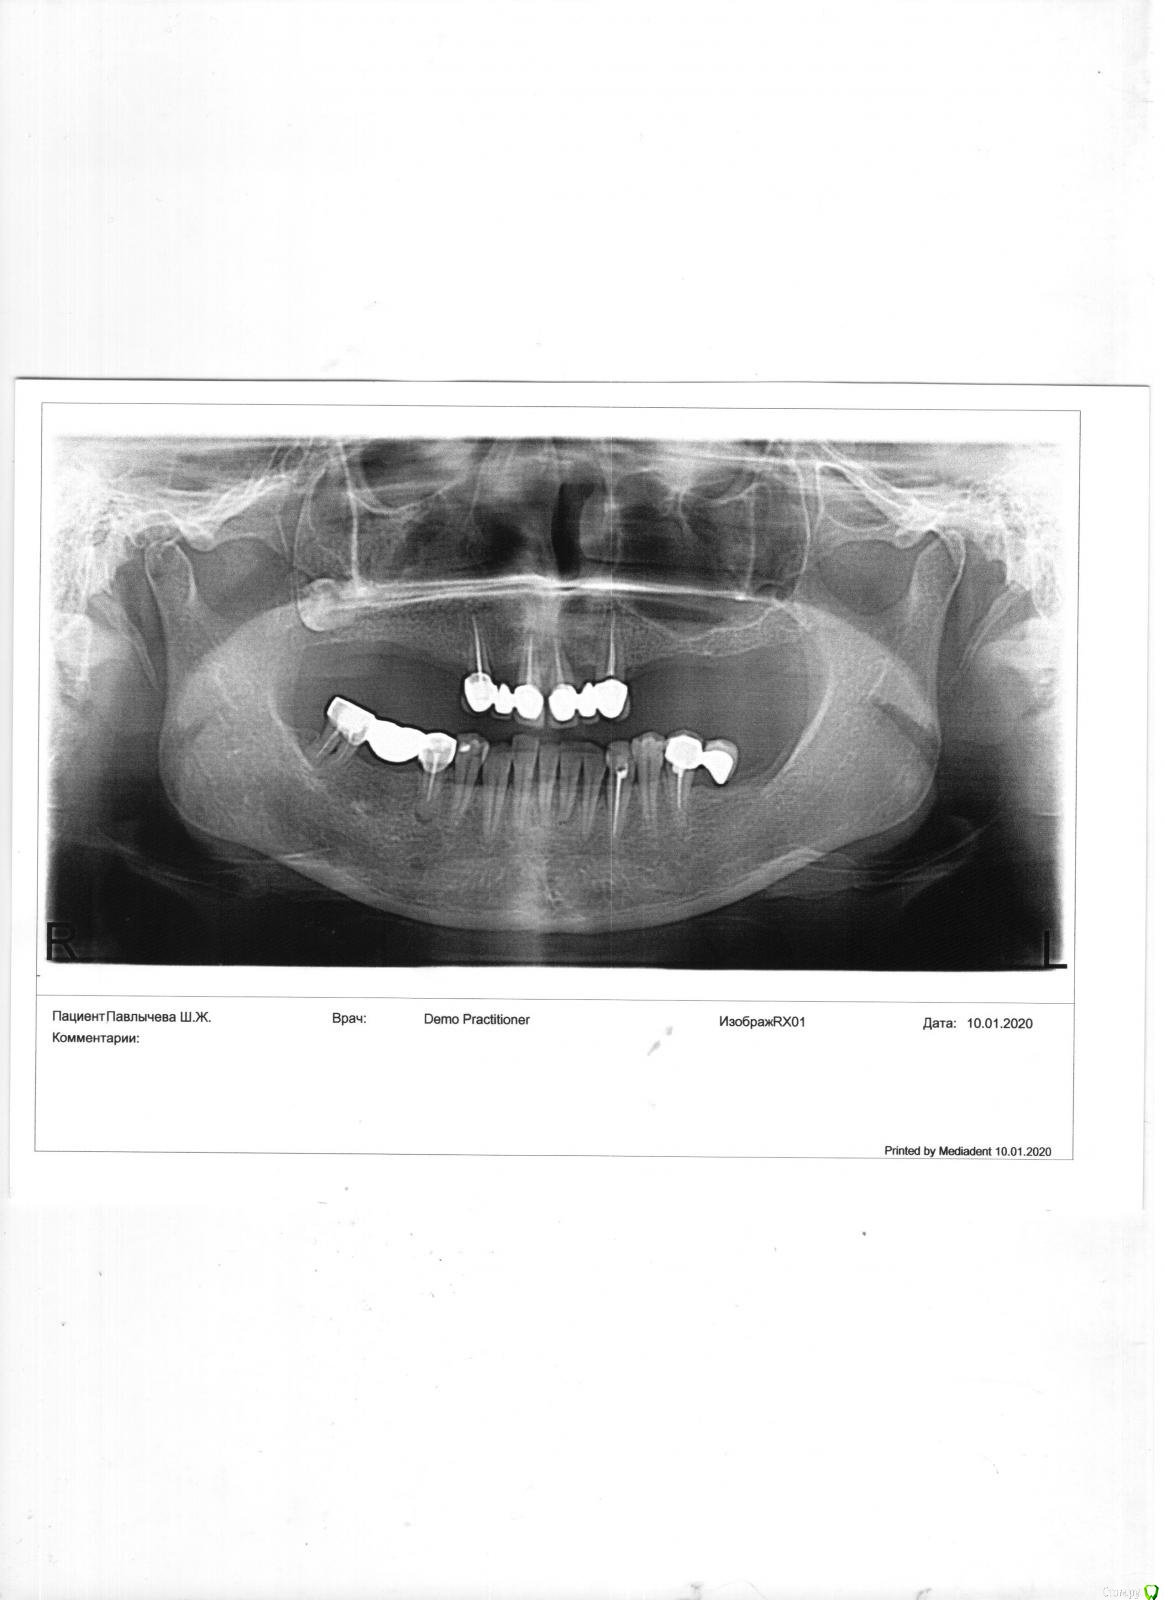

Light70 Опубликовано 11 января, 2020 Поделиться Опубликовано 11 января, 2020 Здравствуйте, женщина 50 лет, в анамнезе - без хронических заболеваний, давление в норме, сахар в норме, почки печень в норме. По сути имеем на верхней челюсти пародонтит, зубы подвижные, бюгельный протез. Есть ли возможность провести костную пластику, чтобы поставить 6 имплантов, а на них протез.? Во вложении панорамный снимок, правда качество чуть хромает))) Нижняя челюсть пока оставляем в том состоянии, лечим десна, протезирование пока повременим или же лучше одновременно? спасибо за ответы Ссылка на комментарий

Light70 Опубликовано 1 февраля, 2020 Автор Поделиться Опубликовано 1 февраля, 2020 Доброго времени суток! Возникла необходимость обратиться за советом во второй раз. Врач предлагает сохранить клыки, несмотря на то что они уже подвижные, провести лечение пародонта, на них поставить мостик, провести синус, на время "приживания" синуса съемный протез не предлагает, обосновывая тем,что протез вытолкнет нарощенную кость. Позже поставить имлантаты и затем по бокам соединить все мостиками.Второй врач предлагает удалить несостоятельные зубы, провести синус, на время установить съемный протез, позже установить имплантаты, затем цельнолитой керамический мост.Прощу помощи в правильном выборе, по стоимости все не дешево и хотелось бы не ошибиться. Спасибо заранее за ответы Ссылка на комментарий